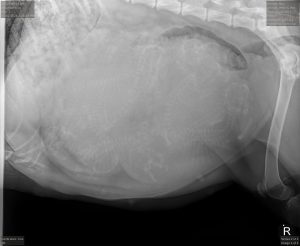

The X-ray brought wonderful news: seven to eight puppies are making themselves comfortable and preparing for their grand debut. If you look closely, you may even spot eight tiny spines—a glimpse of the lives growing quietly and beautifully inside her.